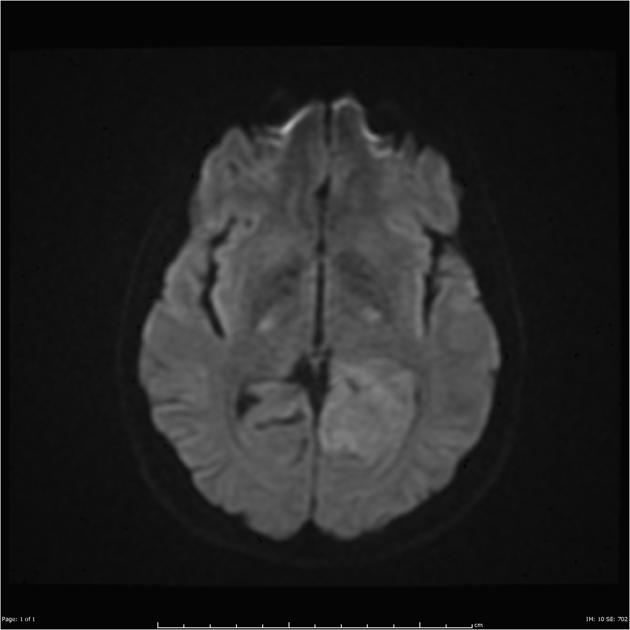

AA DWI

After a careful H&P with attention to neurologic symptoms, time of onset and rate of increase, imaging is critical to localization and diagnosis. Surgery, including a complete debulking if possible is the first line treatment, and sets the stage for the next step. Imaging is predominantly MRI based, with T1 ±gad, T2, FLAIR, diffusion weighted, and gradient echo sequences to identify and localize the extent of disease. Surgery is used to debulk the tumor completely if possible, and if not to obtain tissue for diagnosis.